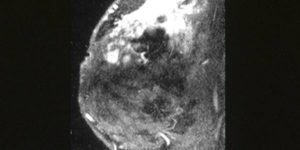

How bacteria may promote breast cancerHow bacteria may promote breast cancer

Researchers at the Johns Hopkins Kimmel Cancer Center have discovered how certain pathogenic bacteria in gut and breast tissue can promote breast cancer development and progression by hijacking a key metabolic enzyme known as spermine oxidase (SMOX). In a study led by Dipali Sharma, Ph.D., professor of oncology, investigators found that exposure to pathogenic bacteria such as Bacteroides fragilis, Fusobacterium nucleatum, and Escherichia coli significantly increased SMOX activity, leading to DNA damage, tumor growth, and metastasis in laboratory and animal models of breast cancer.